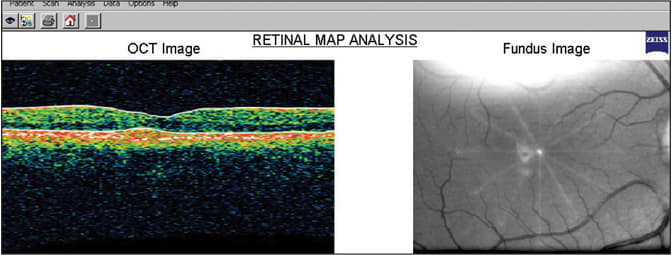

To further evaluate these lesions, we performed an optical coherence tomography (OCT) scan (see "The OCT and Pattern Dystrophies," page 72). The OCT revealed bilateral hyper-reflective, domeshaped elevations within the retinal-pigment epithelium (RPE), just below the fovea (see figure 2). We didn't observe any associated subretinal or intraretinal fluid, which may accompany such findings. The retinal map revealed a normal central retinal thickness of 191μm O.U. Retinal thickness was not affected since the lesion was isolated to the RPE and there was no associated retinal edema.

Figure 2: OCT shows hyper-reflective, dome-shaped elevations within the retinal-pigment epithelium (RPE).

| The ability of the OCT to depict a cross-sectional image of the retina allows you to distinguish overlying and underlying retinal pathology. You can also visualize subtle changes, such as disruption and/or atrophy of the RPE/sensory retina, through the use of OCT imaging. OCT is particularly useful in monitoring progression, since you can take a quantitative and qualitative measurement of associated retinal thickness and pattern size.8 You may observe retinal edema in the OCT of both wet-AMD and a pattern dystrophy of the RPE. Yet, the classic presentation of wet-AMD is characterized by a CNV lesion depicted in the OCT as a fusiform hyper-reflective area above or below the RPE. OCT imaging of pattern dystrophies are as variable as the fundoscopic appearances. The typical finding includes a thickened hyper-reflective lesion within the RPE. Researchers believe these deposits are an abnormal accumulation of lipofuscin — a waste by-product in the RPE linked to free-radical damage.2 Auxiliary testing, such as OCT, is not only valuable in helping determine the diagnosis, but it also aids in the identification of subtle fundoscopic-associated findings, such as subretinal thickening, retinal serous detachment and CNV.9 It is critical to properly diagnose these conditions, so we can manage them appropriately. |